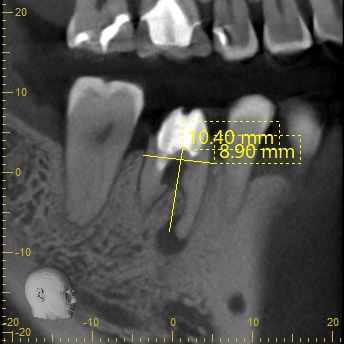

CT(術前・移植前)